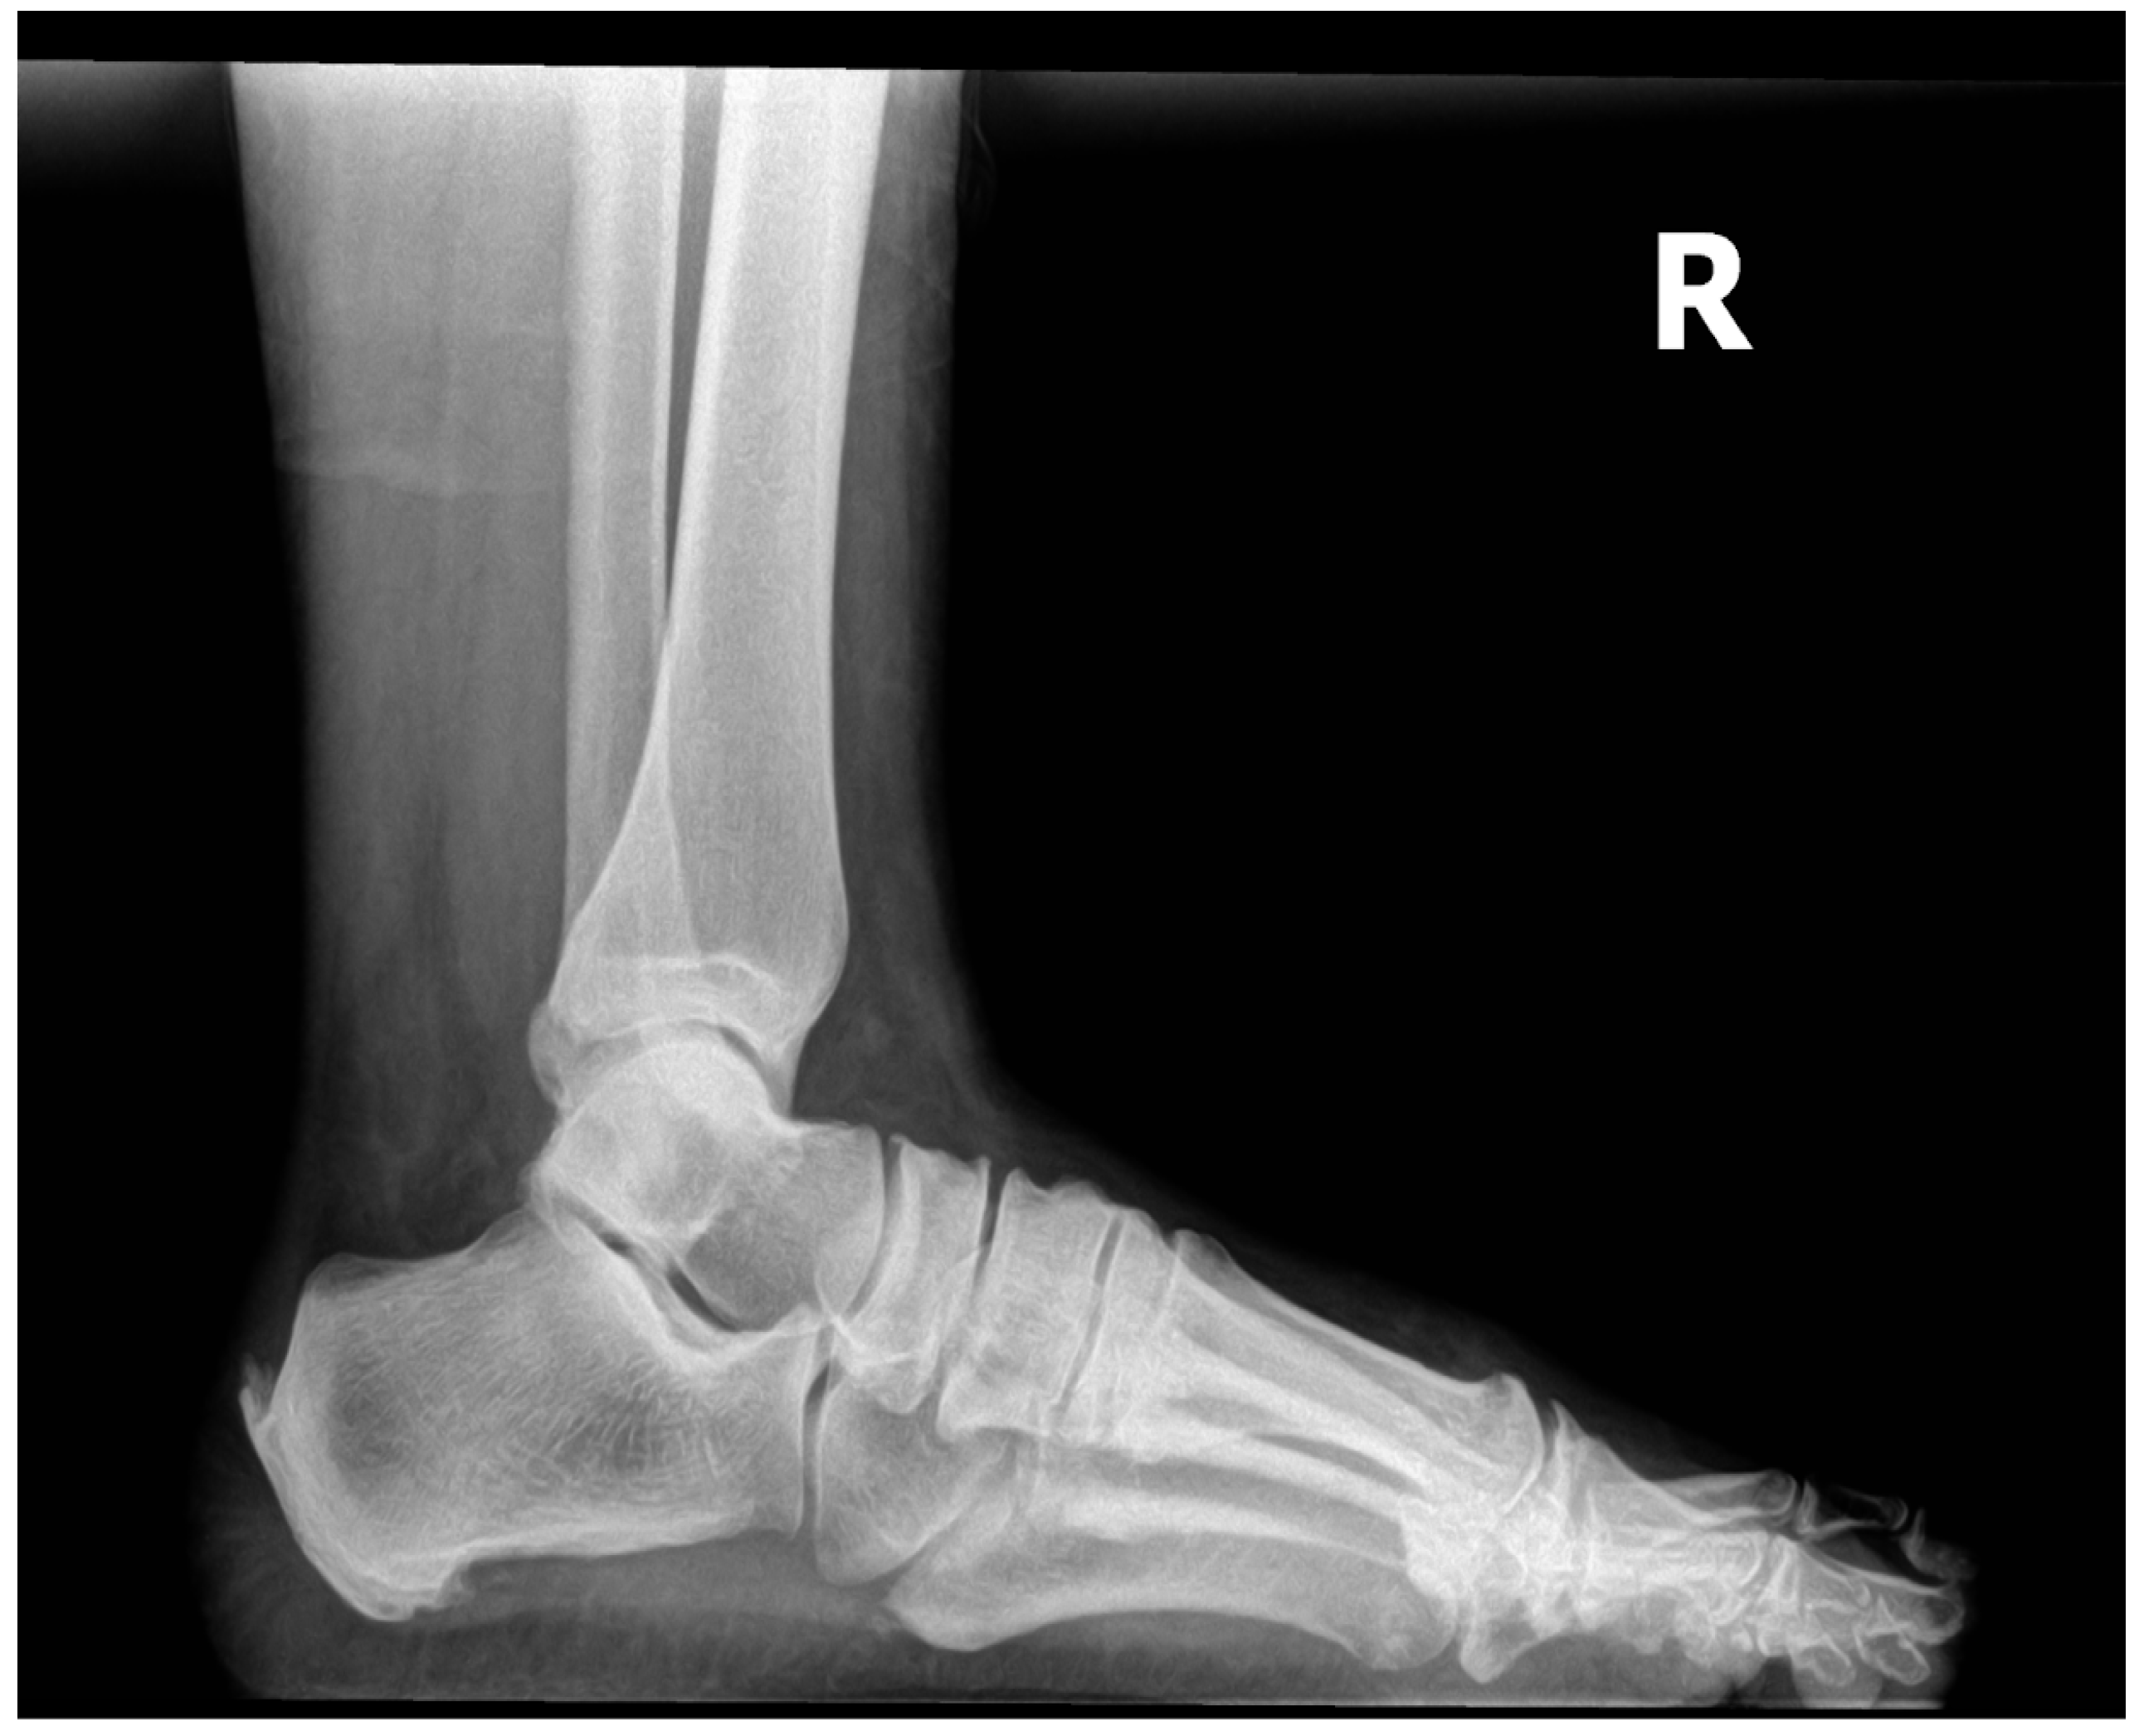

The patient in this study is a 54-year-old female with chronic Achilles tendinosis, enthesopathy at the insertion, and retrocalcaneal exostosis. She has been suffering from her condition for three years after failing several standard care treatment modalities. She presented with a retrocalcaneal exostosis of the right leg, severe pain, and declining surgical intervention (Figure 1). Previously, the patient underwent two procedures performed by a previous surgeon: one successful inferior calcaneal osteotomy and one minimally successful retro calcaneal resection of the contra-lateral foot (Figure 2). Her work requires her to be on her feet 75% of the time, further aggravating the disorder and causing sharp burning pain. To avoid surgery and loss of productive time at work, she sought treatment from Dr. Robert Parker at his clinic, Parker Foot and Ankle, in Houston, Texas. There, she was offered an alternative conservative Wharton's Jelly structural connective tissue to supplement the structural defects in conjunction with EPAT and class IV laser therapy to promote her body’s own repair processes. This study aims to report pain alleviation secondary to supplementing damaged tendon tissue with Wharton’s jelly and priming the local tendon with EPAT and lasers.

Figure 1. 3/21/2023 right foot with no prior procedures.